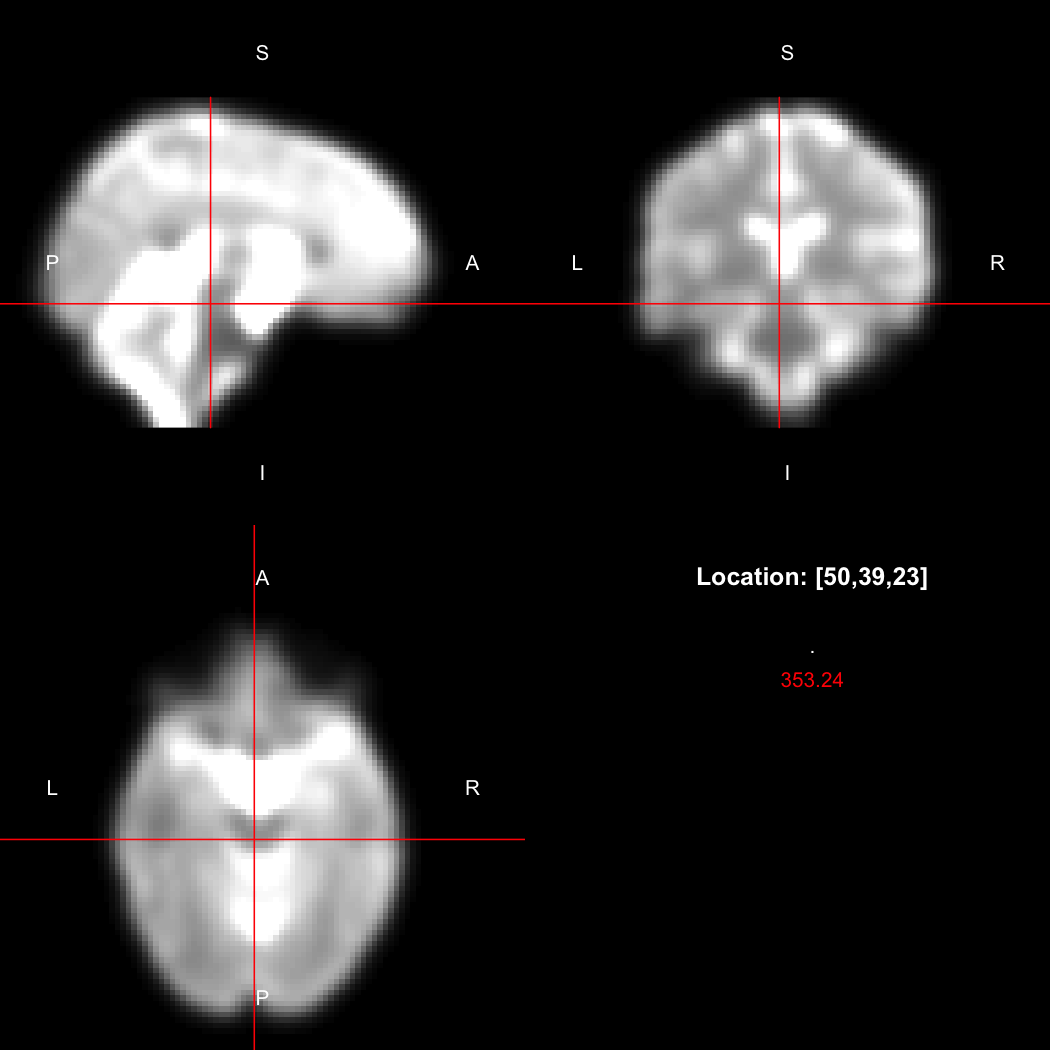

However, the pipe syntax provides an alternative, which can be

further simplified because calling view() on a pipeline

will implicitly run it.

image %>% smooth_gauss(4) %>% view()

## Setting window to (0, 549.9)

Notice now smooth_gauss() is now called with only one

argument, and view() with none, because the input to the

pipe (%>%) is implicitly added first. The benefits to